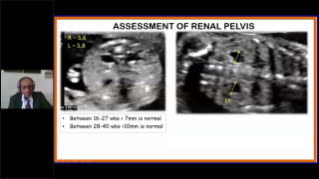

Didukung oleh platform ZST+ yang canggih, solusi cerdas yang lengkap dari Nuewa dirancang secara khusus untuk mendukung kesehatan kaum wanita yang lebih baik selama masa prakehamilan, kehamilan, dan pemulihan pascapersalinan, untuk menghasilkan diagnosis yang komprehensif dan efisien guna memenuhi tantangan klinis yang semakin meningkat.